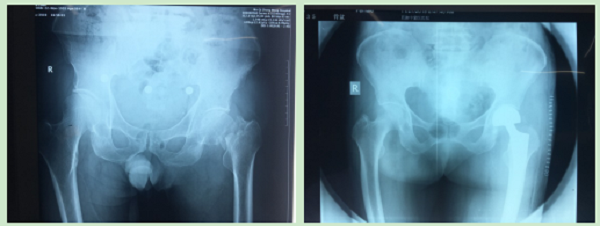

12月份门诊诊疗病例116人次,病种多为腰椎间盘突出症、腰椎管狭窄症、梨状肌紧张综合征、颈椎病、肘管综合征、胸腰椎小关节紊乱症、膝关节骨性关节炎、膝关节滑膜炎、肩关节周围炎、股骨头坏死、距骨坏死、指骨骨髓炎、丹毒、痛风性关节炎及桡骨远端骨折、肱骨骨折、股骨颈骨折、踝关节骨折、掌骨骨折、指骨骨折、跖骨骨折、趾骨骨折、肩关节脱位、指间关节半脱位等。

参与完成髋关节置换术、尺神经前置术、跟骨骨折钢板螺钉取出术、尺桡骨骨折钢板螺钉内固定取出术、掌骨骨折钢板螺钉取出术及清创缝合术等手术六例。